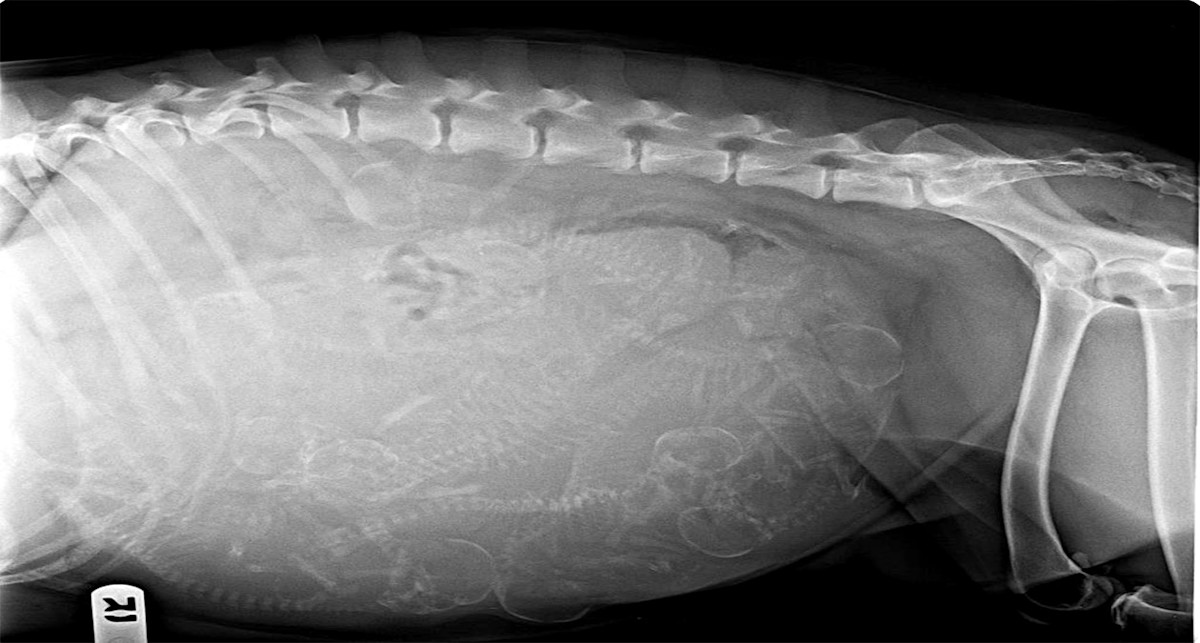

The radiograph’s utility lies in its ability to help us count puppies. Most of our bird dog breeds are naturally excellent mothers and rarely encounter complications during whelping (delivery). However, very small litters—especially when there’s only a single fetus—or extremely large litters can contribute to a higher risk of dystocia, or difficult birth.

If the litter is of medium size, somewhere between 5 and 7 pups in a typical bird dog litter, having an accurate count also gives breeders a benchmark for when they can relax following a stressful, hand-wringing whelping. Waiting around and wondering whether another puppy is on the way can be agonizing.

Developing puppies, especially early in their 9-week gestation, are mostly water and cartilage. The conversion of cartilage to bone (mineralization) begins towards the last two weeks of gestation and peaks during the final week before birth. As more mineralization takes place, the white bones of these pups become more conspicuous among the darker greys of the mother’s belly in the radiograph.